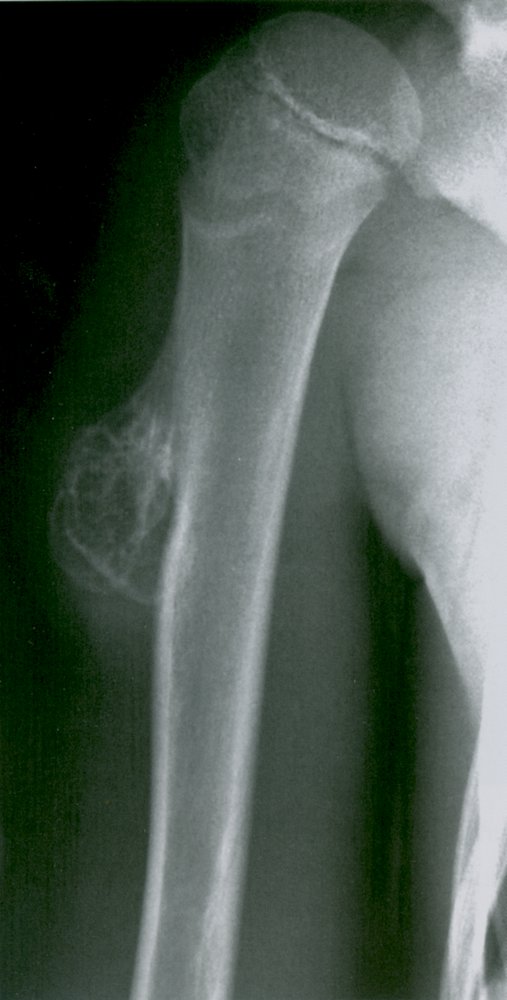

Osteochondroma (cartilaginous exostosis)

• Bony exostosis with cartilage cap

• Peak incidence: 10–30 years

• Sex: ♂ > ♀

• Metaphysis of long bones

• Most common primary benign bone tumor

• Usually asymptomatic, but can be painful and palpable near the ends of long bones

• X-ray: pediculated or sessile mass

• Disease variant: hereditary multiple exostoses (malignant degeneration may occur)

• Transformation into chondrosarcoma is rare

• Description

• Bony outgrowth (exostosis) with a cartilaginous cap on the surface of long bones adjacent to growth plates

• Contains a marrow space that is continuous with the underlying bone

• Epidemiology

• Peak incidence: 10–30 years [2]

• Sex: >

• Clinical features

• Typically located in metaphysis of long bones

• Subtypes and variants: hereditary multiple exostoses (EXT)

• Definition: autosomal dominant disorder with multiple exostoses

• Most commonly caused by autosomal dominant inheritance of a germline mutation in the EXT tumor suppressor gene.

• Malignant degeneration to chondrosarcoma may occur (∼ 5% of cases).

• Diagnostics: x-ray shows pedunculated; or sessile; lesion on the surface of the metaphysis of long bones

• Treatment: excision of tumor in symptomatic cases

• Complications: Approx. 1% transform into chondrosarcoma.